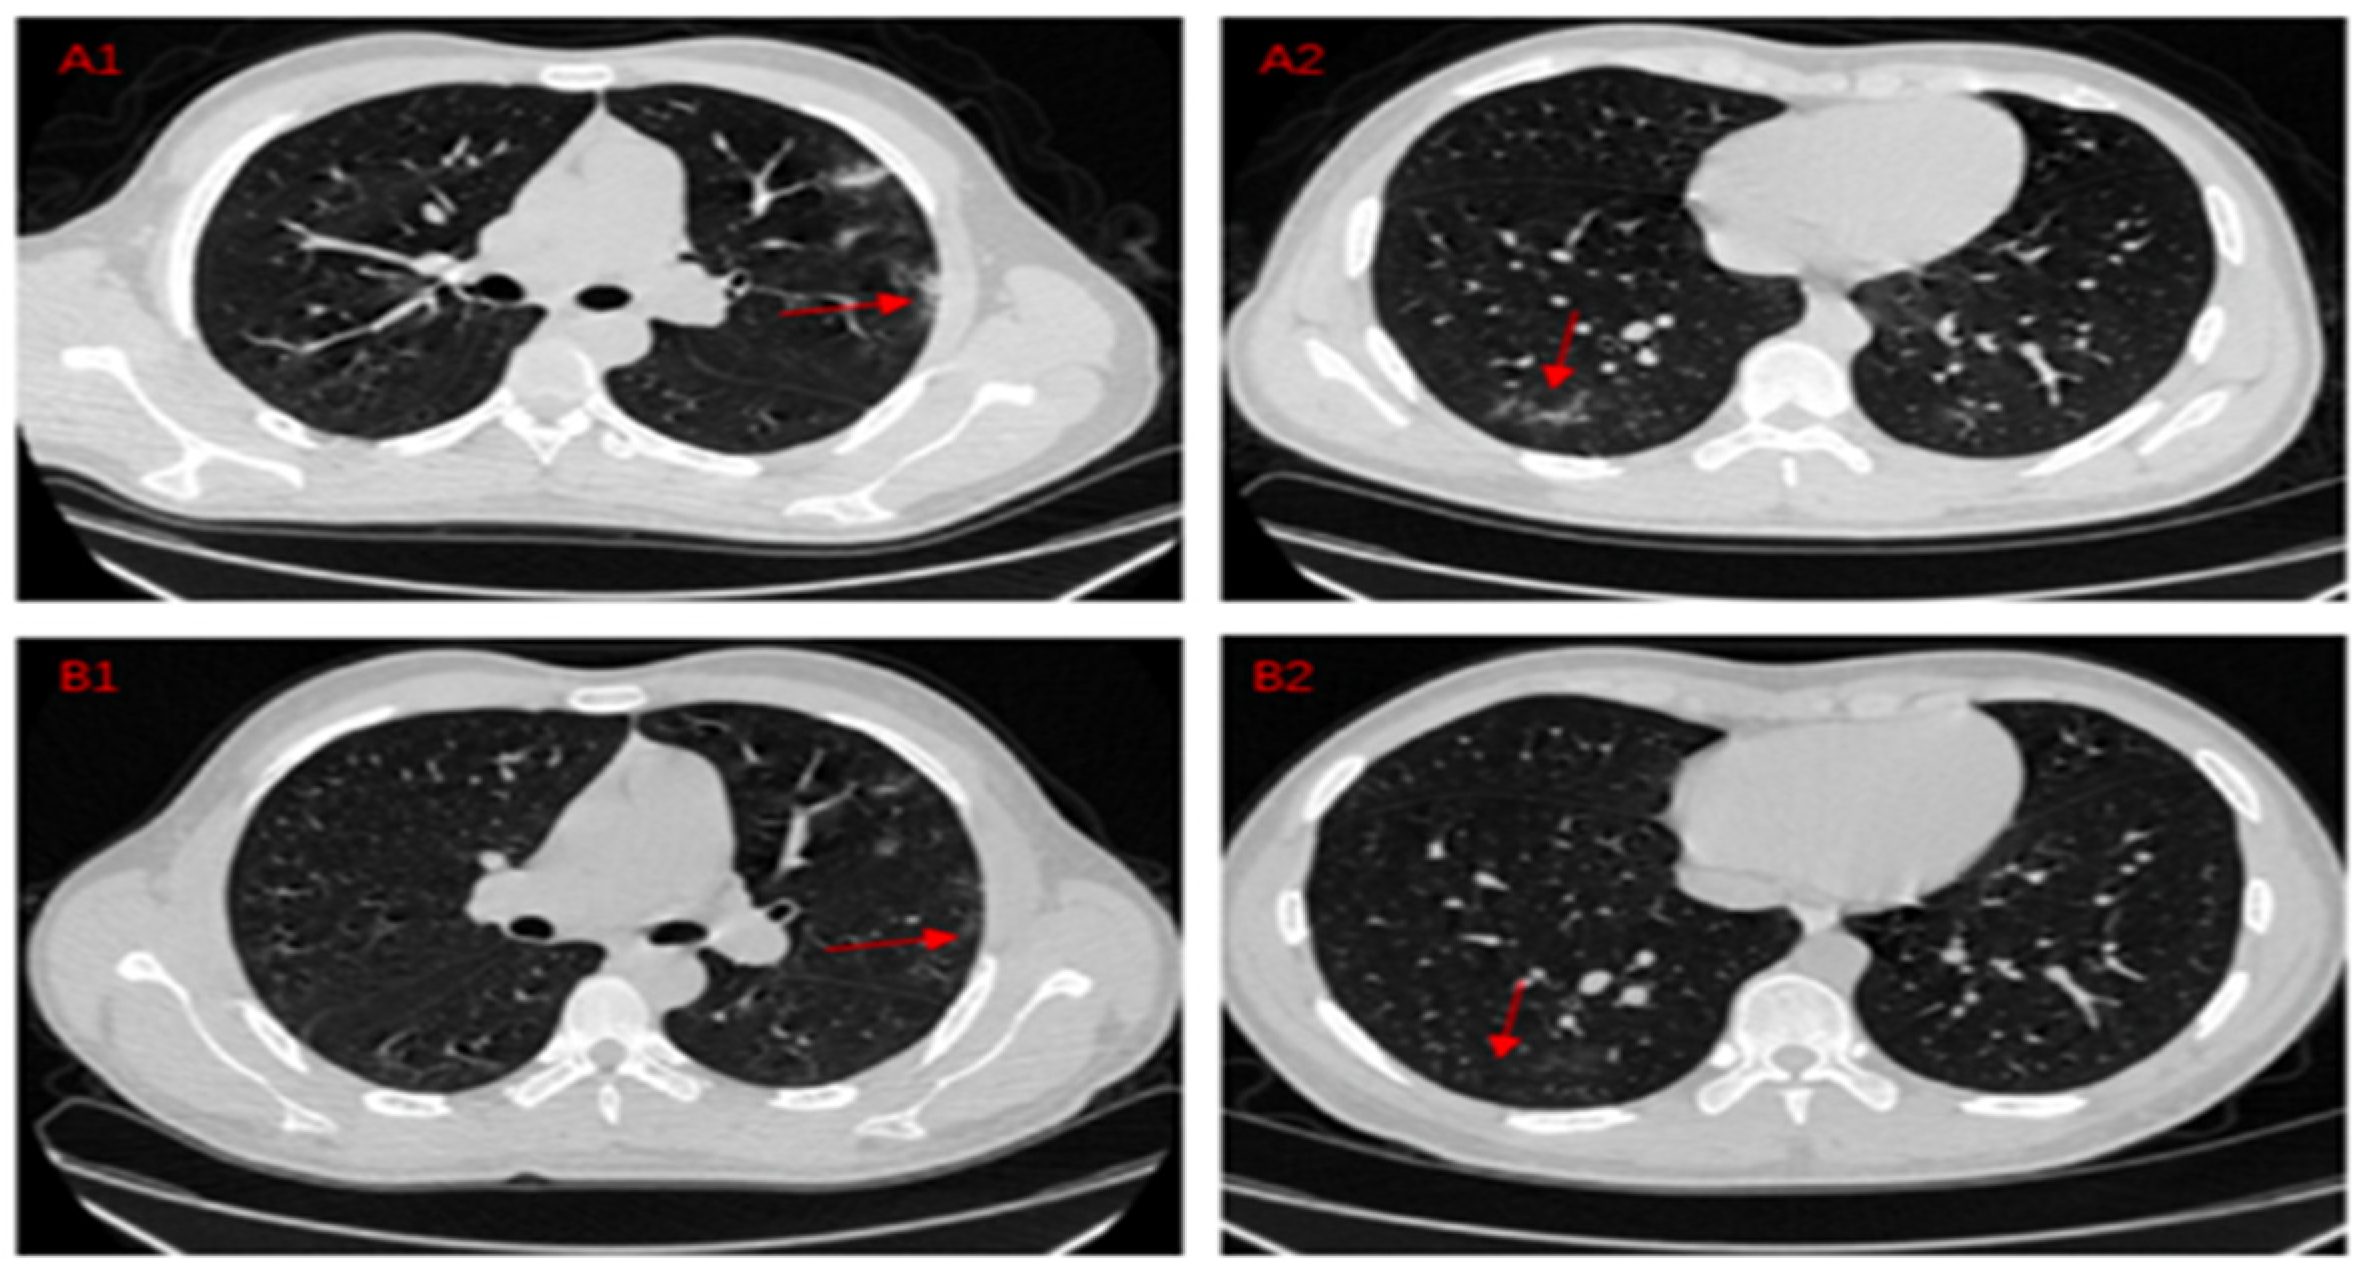

- Fan, D.P.; Zhou, T.; Ji, G.P.; Zhou, Y.; Chen, G.; Fu, H.; Shen, J.; Shao, L. Inf-net: Automatic COVID-19 lung infection segmentation from ct images. IEEE Trans. Med. Imaging 2020, 39, 2626–2637. [Google Scholar] [CrossRef] [PubMed]